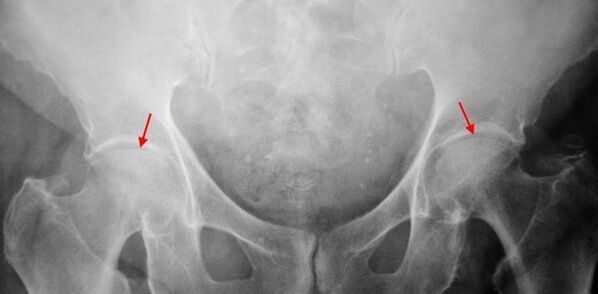

In the patient's X list suffering from first -degree coxarthrosis, minor changes are determined: moderate unequal narrowing of the joint gap, as well as bone growth around the outer or internal edge of the acetabulum in the absence of changes from the head and neck of the femur.

In X -ray images for second -degree coxarches, significant unequal narrowing of the joint gap is determined (more than half from normal height).The femoral head moves a little up, deforms and increases in size, and their contours become unequal.Bone growths with this degree of coxarcher appear not only in the internal, but also on the outer edge of the acetabulum and leave the cartilage.

In the radiographs for third grade coxarthrosis, acute narrowing of the articular gap, a pronounced expansion of the thigh head and multiple bone growth is detected.

The diagnosis of coxarthrosis is based on clinical signs and additional studies data, the main one of which is the radiography.In many cases, X -rays allow not only the degree of coxarcher, but also the cause of their occurrence.So, for example, an increase in the diffessional angle of the neck, the scenes and the flattening of the acetabulum indicate dysplasia, and the changes in the shape of the proximal part of the femur are indicated that cookardrosis is a consequence of the disease of pertes or the youth epiphysitic.In the radiographs of patients with coxarchesis, changes that indicate injuries can also be detected.